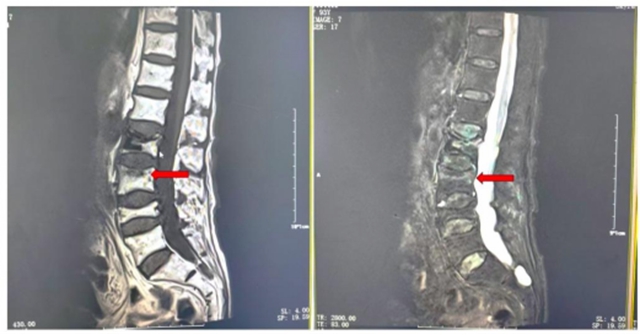

来到泸州市人民医院神经脊柱外科门诊检查后发现,她的腰椎第三节已被骨质疏松"蛀"成了压缩性骨折。

但是,医学的"魔法"总在绝境中闪光。神经脊柱外科团队化身"骨骼修复师",为她实施了腰3椎体经皮椎体成形术。

医生通过仅0.5厘米的针孔(约绿豆大小),将特制"骨水泥"精准注入骨折椎体。

“骨水泥”这种医用材料在10分钟内就会凝固,像3D打印般重塑椎体结构,既能立即稳定骨折部位,又能减轻疼痛。